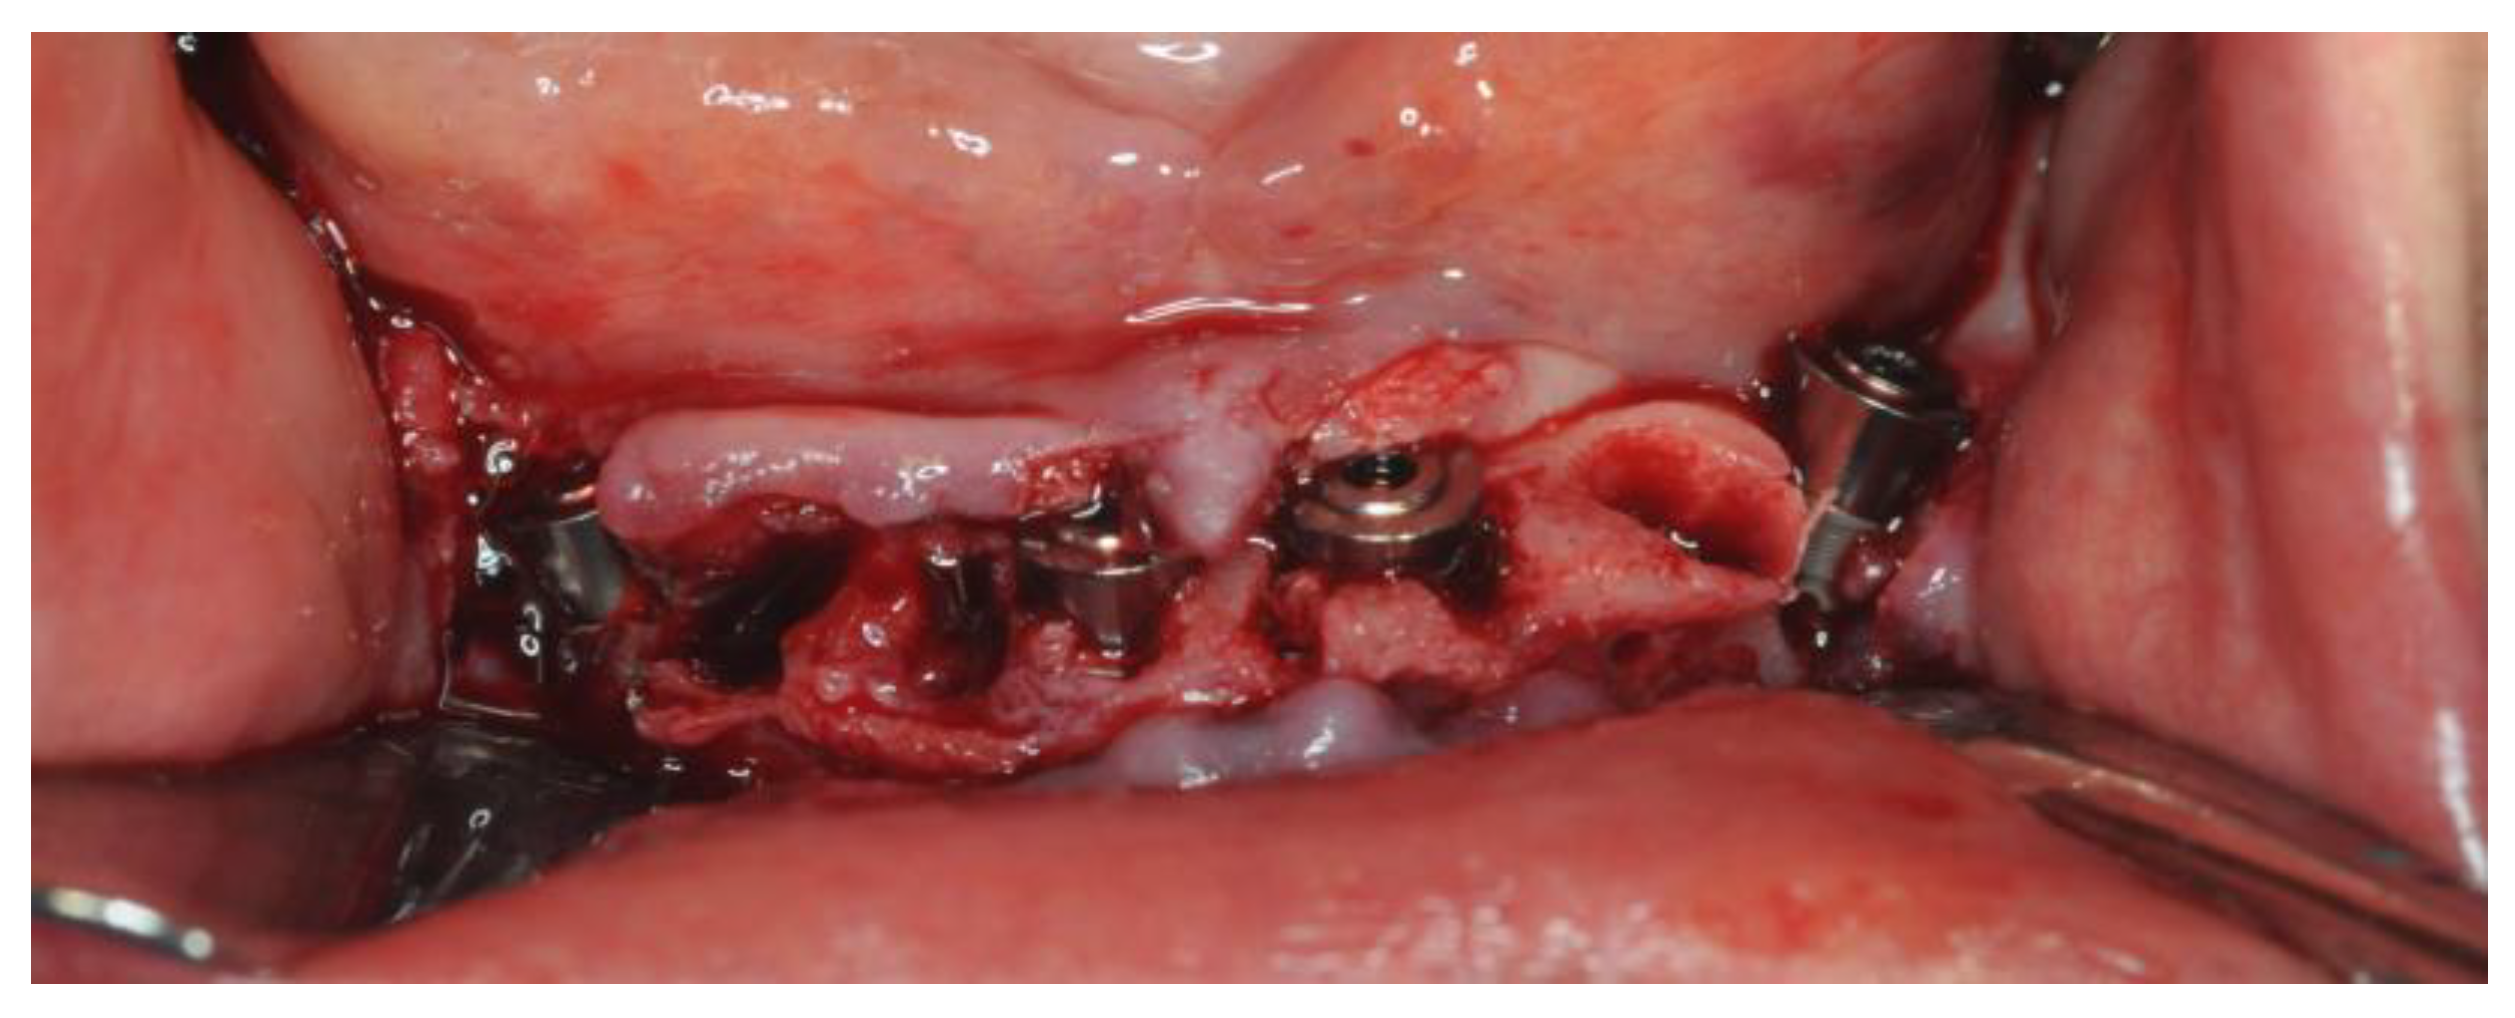

2.4. Surgery